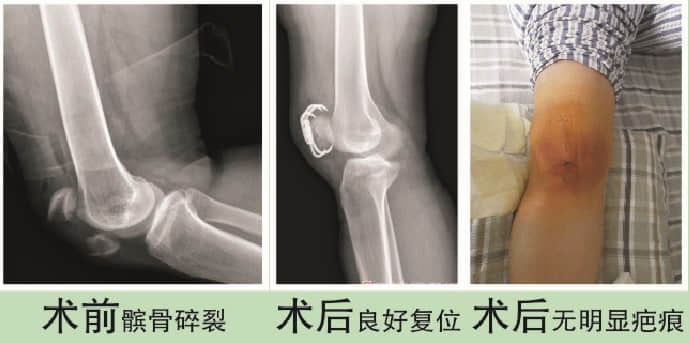

钟丽娟,女,34岁,因右髌粉碎性骨折入院。入院后立即行开放复位内固定术,切口使用美容缝合。手术骨折复位满意,固定牢靠,术后1周下床活动。

钟丽娟,女,34岁,因右髌粉碎性骨折入院。入院后立即行开放复位内固定术,切口使用美容缝合。手术骨折复位满意,固定牢靠,术后1周下床活动。